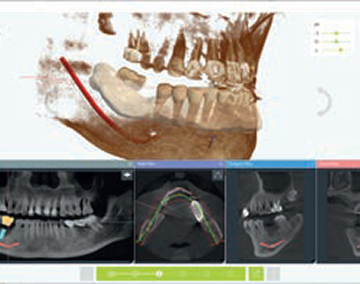

Draw Nerve

54yrs/Female | Implant Parts #35,36,37 | Fix Size: SuperLine FXS4012 | Guide Kit: Full Kit

It takes at least one week to produce through a request from the center, but if you design your own using Dentium Digital Guide Software, you can produce it within 30 minutes to an hour. When weeding the guide, pay attention to the ct alignment, and when making the guide, the undercut and border should be well set to fit the patient's mouth. It is recommended to use the anchor pin function for stability.